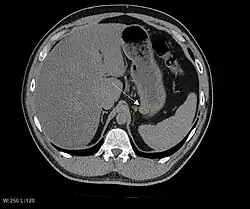

The purpose of radiologic imaging is to locate the lesion, evaluate for signs of invasion and detect metastasis. Features of GIST vary depending on tumor size and organ of origin. The diameter can range from a few millimeters to more than 30 cm. Larger tumors usually cause symptoms in contrast to those found incidentally which tend to be smaller and have better prognosis.[4][20] Large tumors tend to exhibit malignant behavior but small GISTs may also demonstrate clinically aggressive behavior.[21]

Preferred imaging modalities in the evaluation of GISTs are CT and MRI,[23]: 20–21 and, in selected situations, endoscopic ultrasound. CT advantages include its ability to demonstrate evidence of nearby organ invasion, ascites, and metastases. The ability of an MRI to produce images in multiple planes is helpful in determining the bowel as the organ of origin (which is difficult when the tumor is very large), facilitating diagnosis.

As the tumor grows it may project outside the bowel (exophytic growth) and/or inside the bowel (intraluminal growth), but they most commonly grow exophytically such that the bulk of the tumor projects into the abdominal cavity. If the tumor outstrips its blood supply, it can necrose internally, creating a central fluid-filled cavity with bleeding and cavitations that can eventually ulcerate and communicate into the lumen of the bowel. In that case, barium swallow may show an air, air-fluid levels or oral contrast media accumulation within these areas.[21][25] Mucosal ulcerations may also be present. In contrast-enhanced CT images, large GISTs appear as heterogeneous masses due to areas of living tumor cells surrounding bleeding, necrosis or cysts, which is radiographically seen as a peripheral enhancement pattern with a low attenuation center.[20] In MRI studies, the degree of necrosis and bleeding affects the signal intensity pattern. Areas of bleeding within the tumor will vary its signal intensity depending on how long ago the bleeding occurred. The solid portions of the tumor are typically low signal intensity on T1-weighted images, are high signal intensity on T2-weighted images and enhanced after administration of gadolinium. Signal-intensity voids are present if there is gas within areas of necrotic tumor.[22][26][27]

Malignancy is characterized by local invasion and metastases, usually to the liver, omentum and peritoneum. However, cases of metastases to bone, pleura, lungs and retroperitoneum have been seen. In distinction to gastric adenocarcinoma or gastric/small bowel lymphoma, malignant lymphadenopathy (swollen lymph nodes) is uncommon (<10%) and thus imaging usually shows absence of lymph node enlargement.[20] If metastases are not present, other radiologic features suggesting malignancy include: size (>5 cm), heterogeneous enhancement after contrast administration, and ulcerations.[4][20][28] Also, overtly malignant behavior (in distinction to malignant potential of lesser degree) is less commonly seen in gastric tumors, with a ratio of behaviorally benign to overtly malignant of 3-5:1.[4] Even if radiographic malignant features are present, these findings may also represent other tumors and definitive diagnosis must be made immunochemically.